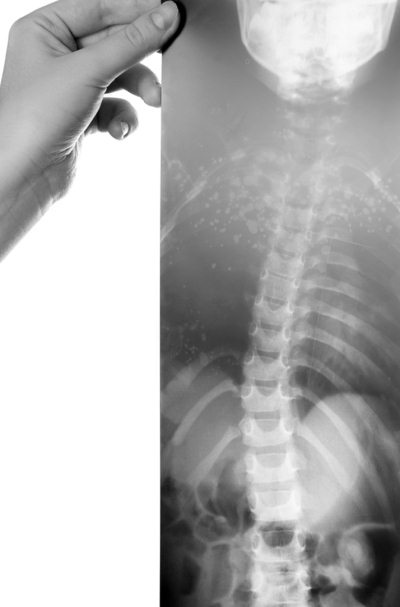

Иллюстрация к книге — Правильная осанка. Как спасти ребенка от сколиоза [i_004.jpg]

Под сколиозом (от греч. scoliosis — искривление) подразумевают искривление позвоночника во фронтальной плоскости, то есть в правую или левую сторону. Данный вид нарушения осанки может возникать в шейном, грудном или поясничном отделах позвоночника. Когда наблюдается искривление по одной боковой дуге, сколиоз называется простым. Если же искривление позвоночника образуется по нескольким дугам в разные стороны, оно считается сложным. В случае, когда искривлению подвергнут весь позвоночный столб, говорят о тотальном сколиозе. Если появляется только боковой изгиб, то говорят о сколиотической осанке. При этом позвоночник стоящего прямо ребенка выглядит как сплошная дуга бокового искривления и наблюдается асимметрия между правой и левой половинами туловища. Если же одновременно с боковым изгибом происходит поворот позвоночника вокруг вертикальной оси (торсия), то говорят о сколиотической болезни. Этот поворот усугубляет деформацию грудной клетки, вызывая ее асимметрию. В результате внутренние органы смещаются и сжимаются.

Нарушения осанки в виде появления боковых изгибов позвоночника наиболее часто развиваются в детском возрасте, особенно у детей дошкольного и младшего школьного возраста. Зачастую сколиозы называют школьными, поскольку именно у детей школьного возраста они выражены наиболее отчетливо. Непременным условием развития искривлений является слабость мышц и связок позвоночника и грудной клетки. Довольно часто сколиоз сочетается с плоской спиной или вялой осанкой.